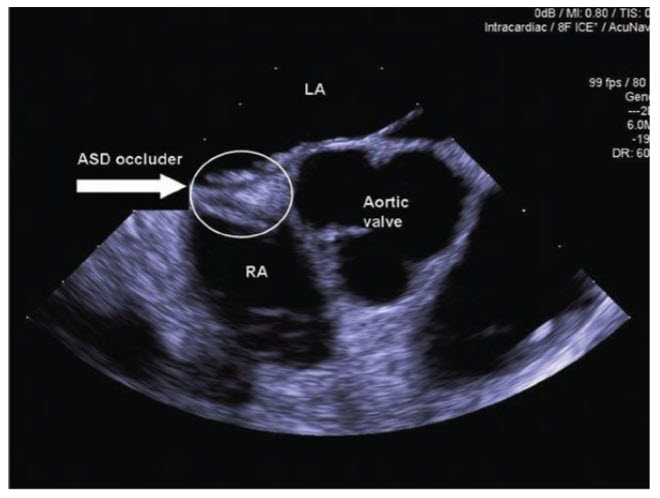

Secundum ASD. The majority of secundum ASDs can be closed with a percutaneous catheter technique. ASD closure is indicated for RA and RV enlargement with or without symptoms. Small ASDs (<5 mm) with no evidence of volume overload do not require closure unless associated with cryptogenic paradoxical embolism. Sinus venous, coronary sinus, and primum defects are not amenable to device closure (Fig. below).

An atrial septal defect (ASD) occlusion device is seen positioned across a secundum ASD. The image was acquired using intracardiac echocardiography and consists of a short-axis view of the heart demonstrating the aortic valve and the interatrial septum dividing the left atrium (LA) and right atrium (RA).